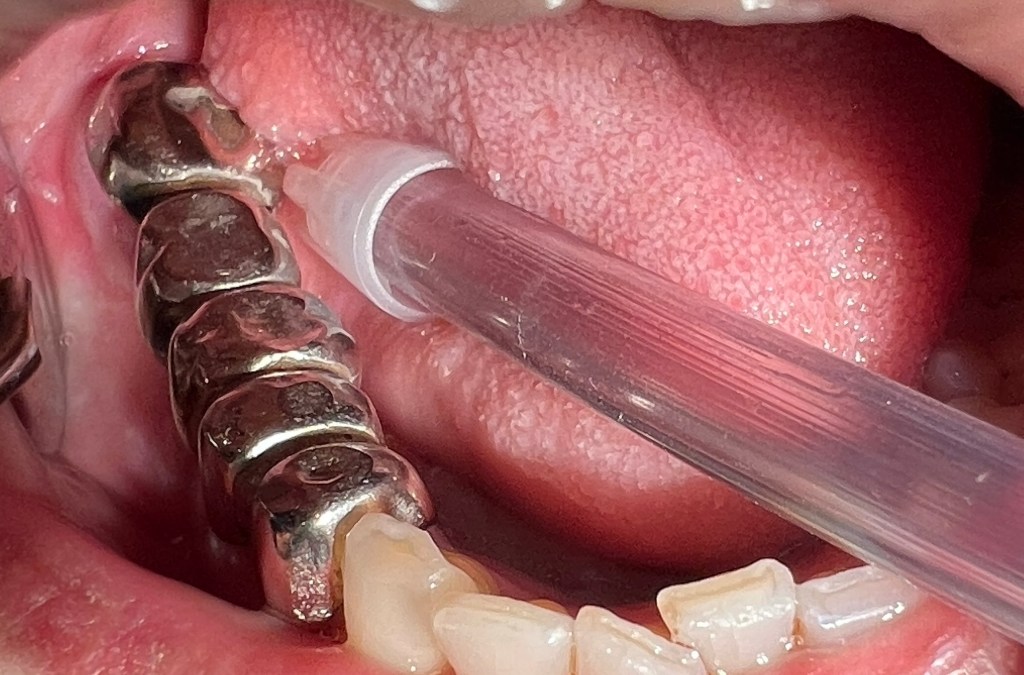

Don’t Remove. (before X-ray) radix-ento พบได้ในคนไทย 12.7% Germination X-ray ช่วยให้เห็นสิ่งที่ซ่อนอยู่ภายใน สังเกต furcation ก็รู้ว่าฟัน Perio Mermaid Premolar ให้สังเกตที่ mouth mirror เห็นถึงความฝ้ามัว เป็น Br พม่าครับ alloy ไม่แข็งมาก X-ray เท่านั้นจึงจะรื้อได้ ผมจะชอบวัดความยาวของฟันบ่อยๆ เทียบกับความยาวในใจที่เดาเอาไว้ RCT incomplete ใครสังเกตเห็นความผิดปกติบ้างครับ? ถึงกับต้องถ่ายทุกมุมเลยซี่นี้ remove ฟัน Crowding เป็น PVC ล้อมด้วยฟัน RCT อย่าลืม X-ray ก่อนถอนนะครับ Share this: Share on X (Opens in new window) X Share on Facebook (Opens in new window) Facebook Like Loading... Uncategorized